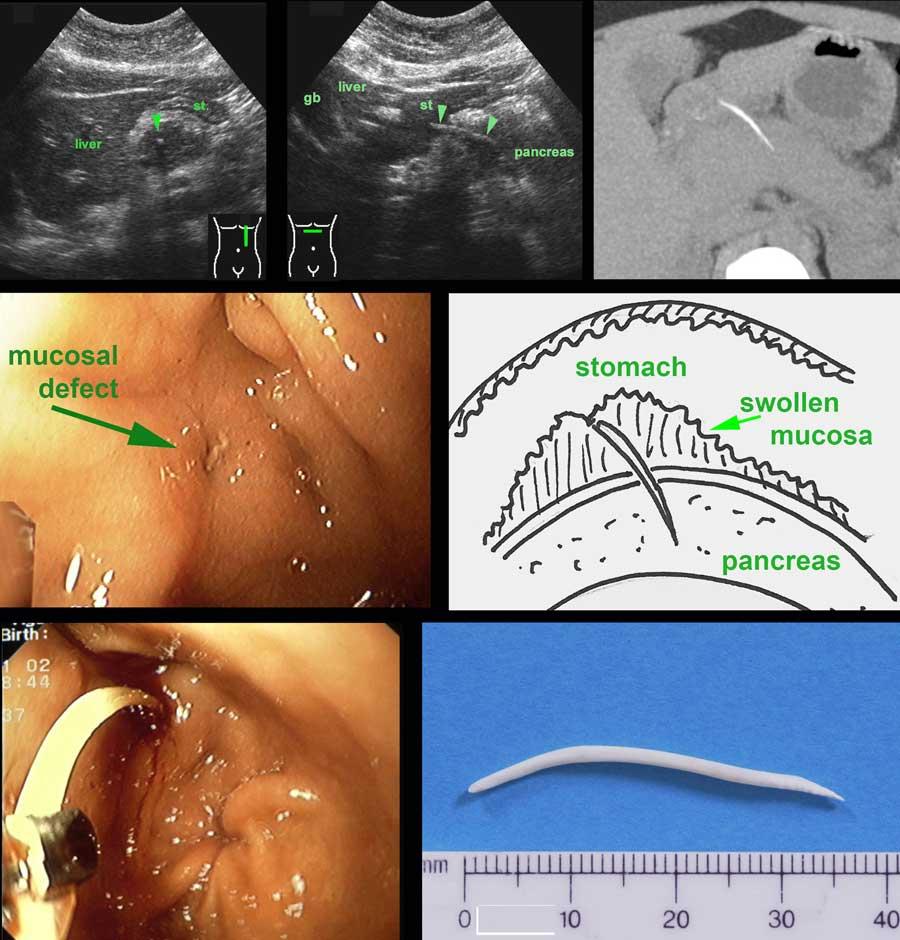

Bệnh nhân nữ 37 tuổi với triệu chứng đau thượng vị tiến triển trong 4 ngày.

Siêu âm phát hiện một cấu trúc đường cong phản âm (đầu mũi tên) kéo dài từ dạ dày (st.) vào tụy đang sưng nề, nghi ngờ là xương cá. (gb=túi mật).

CT không tiêm thuốc cản quang xác nhận có xương cá cắm vào tụy.

Khi nội soi dạ dày, không thấy xương cá, chỉ thấy một khiếm khuyết niêm mạc nhỏ tạo ra một số sợi fibrin.

Chúng tôi cho rằng đây là điểm xương cá đã xuyên qua, trong khi phần đầu còn lại của xương cá bị “chôn vùi” trong lớp niêm mạc phù nề phản ứng của thành sau dạ dày (xem hình vẽ).

Được khích lệ bởi thông tin này, bác sĩ nội soi đã thực hiện thao tác thăm dò sâu bằng kẹp lớn, và cuối cùng đã thành công.

Bệnh nhân hồi phục hoàn toàn và cho biết đã ăn cá “jarabaka” một tuần trước đó, một loại cá của Suriname, nổi tiếng với hương vị thơm ngon và xương sắc nhọn.